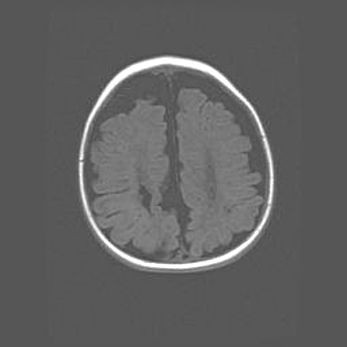

Открытая гидроцефалия.

Возраст: 9 месяцев 12 дней

Вес: 6800 г

Пол: мужской

Окружность головы: 41,5 см

Срок гестации: 28 недель

Гидроцефалия головного мозга у новорожденных имеет характерный признак: опережающий рост окружности головы приводит к визуально хорошо определяемой гидроцефальной форме сильно увеличенного в объёме черепа. Детские неврологи определяют следующие симптомы гидроцефалии у грудничков: выбухающий напряжённый родничок, частое запрокидывание головы, смещение глазных яблок к низу.